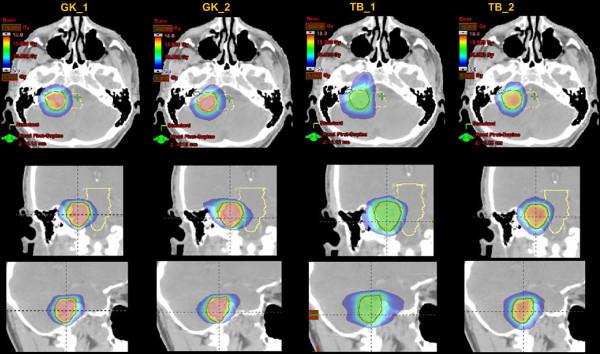

Twelve patients with vestibular schwannoma (VS, n = 6) or cavernous sinus meningioma (CSM, n = 6) were planned for both SRS using volumetric modulated arc therapy (VMAT) by RA. 104 MV flattening filter free photon beams with a maximum dose rate of 2400 MU/min were selected. Data were compared against plans optimised for GK. A single dose of 12.5 Gy was prescribed. The primary objective was to assess treatment plan quality. Secondary aim was to appraise treatment efficiency.

For VS, comparing best GK vs. RA plans, homogeneity was 51.7 ± 3.5 vs. 6.4 ± 1.5%; Paddick conformity Index (PCI) resulted 0.81 ± 0.03 vs. 0.84 ± 0.04. Gradient index (PGI) was 2.7 ± 0.2 vs. 3.8 ± 0.6. Mean target dose was 17.1 ± 0.9 vs. 12.9 ± 0.1 Gy. For the brain stem, D(1cm3) was 5.1 ± 2.0 Gy vs 4.8 ± 1.6 Gy. For the ipsilateral cochlea, D(0.1cm3) was 1.7 ± 1.0 Gy vs. 1.8 ± 0.5 Gy. For CSM, homogeneity was 52.3 ± 2.4 vs. 12.4 ± 0.6; PCI: 0.86 ± 0.05 vs. 0.88 ± 0.05; PGI: 2.6 ± 0.1 vs. 3.8 ± 0.5; D(1cm3) to brain stem was 5.4 ± 2.8 Gy vs. 5.2 ± 2.8 Gy; D(0.1cm3) to ipsi-lateral optic nerve was 4.2 ± 2.1 vs. 2.1 ± 1.5 Gy; D(0.1cm3) to optic chiasm was 5.9 ± 3.1 vs. 4.5 ± 2.1 Gy. Treatment time was 53.7 ± 5.8 (64.9 ± 24.3) minutes for GK and 4.8 ± 1.3 (5.0 ± 0.7) minutes for RA for schwannomas (meningiomas).